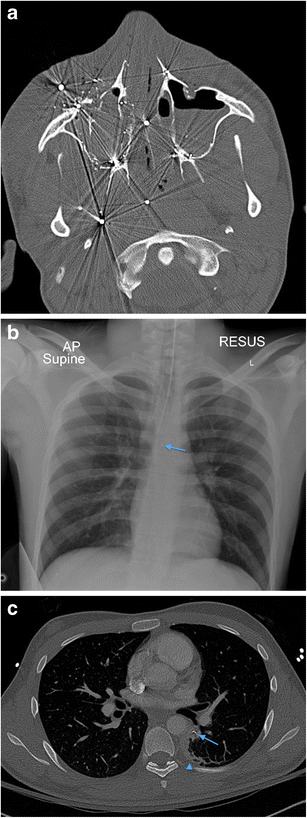

a Coronal reformatted MDCTA image of a 16-year-old man who sustained a gunshot injury to the right superior zone 2. There is a large haematoma in the right submandibular region, extending medially into the ipsilateral sublingual space and oral cavity, as well as laterally into the supero-lateral facial and buccal soft tissues. The comminuted fracture of the affected posterior aspect of the body of the right hemimandible has yielded numerous fracture fragments which have potentiated soft tissue damage. Because of marked haematoma and haemorrhagic debris affecting the oral cavity and oropharynx, emergency per-oral endotracheal intubation could not be performed and the patient has emergency cricothyroidotomy cannulation in situ. b Axial MDCTA image of the same patient as in a. The extensive soft tissue haematoma and oedematous swelling of the right oral cavity, oropharynx, sublingual space, submandibular space and facial region is evident as well as the in-driven comminuted bone fragments arising from the right hemimandible. Bilateral soft tissue emphysema is present. Note the absence of per-oral endotracheal intubation. c Three-dimensional VRT of the mandible demonstrating the relatively focal comminution of the right hemimandible caused by bullet impact and the resultant dispersal of in-driven bone fracture fragments. Three-dimensional volume-rendered images can be particularly helpful to the maxillofacial surgeon managing such injuries and also in assisting criminal police investigations and court presentations